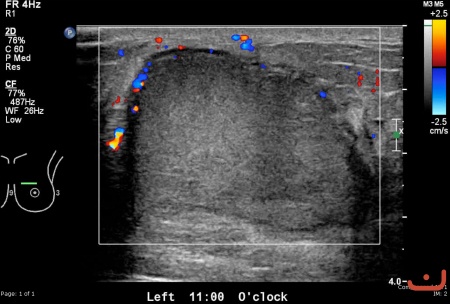

Benign solid mass

Date

Friday, 22 May 2015

File size of the original image

103.02 KB (451 x 304 px)